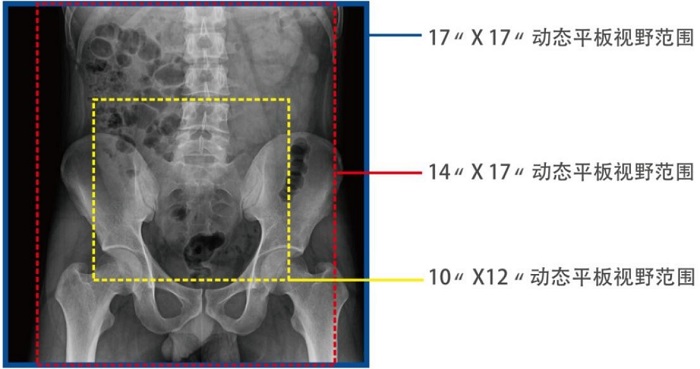

動態(tài)DRF在肛腸科檢查中優(yōu)勢明顯。首先,17×17英寸大幅面成像,對于食道、胃、腸、結(jié)腸等大范圍成像部位,可一次曝光完成,極大減少了患者的輻射劑量和檢查時間,且空間分辨率高,與傳統(tǒng)胃腸機相比,圖像質(zhì)量大幅提升。